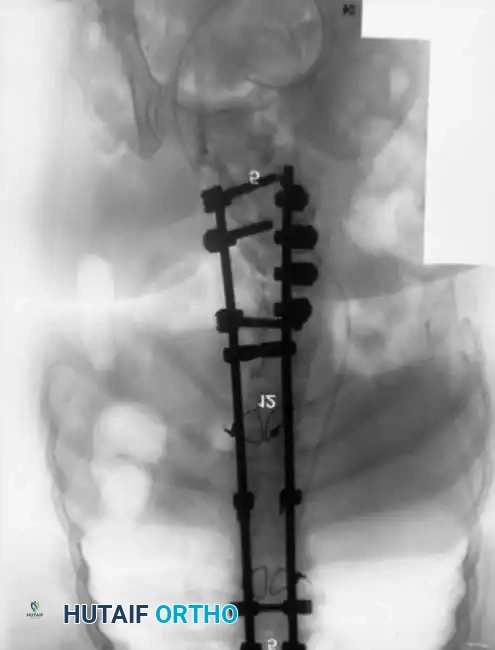

Associated Surgical & Radiographic Imaging

Posterior Instrumentation Techniques

Pedicle screw fixation is the anchor of choice, providing three-column control even in the absence of posterior elements. Free-hand techniques are often supplemented with intraoperative fluoroscopy or robotic navigation due to the highly dysmorphic pedicle anatomy.

Copious amounts of bone graft (autograft from the iliac crest, combined with allograft and osteoinductive biologics) are laid into the lateral gutters and over the decorticated transverse processes to ensure a robust fusion mass.

Severe Lumbosacral Deformity: The L5 Vertebrectomy

In cases of extreme lumbosacral kyphosis or spondyloptosis associated with myelomeningocele, a standard fusion is insufficient to restore sagittal balance. Gaines described a powerful two-stage L5 vertebrectomy technique to address this.

Stage 1 (Anterior): The L5 vertebral body and adjacent discs are completely excised via an anterior approach, decompressing the anterior neural elements and mobilizing the spine.

Stage 2 (Posterior): The patient is flipped prone. The L4 vertebra is then reduced directly onto the sacrum (S1), effectively shortening the spine, correcting the kyphosis, and allowing for rigid posterior pedicle screw fixation from the lumbar spine to the pelvis.